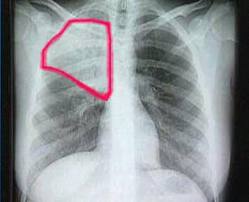

La neumonía, pulmonía o neumonitis es una enfermedad infecciosa e inflamatoria que consiste en la infección de los espacios alveolares de los pulmones.

La neumonía puede afectar a un lóbulo pulmonar completo, a un segmento de lóbulo, a los alvéolos próximos a los bronquios o al tejido intersticial, la neumonía hace que el tejido que forma los pulmones, se vea enrojecido, hinchado y se torne doloroso.